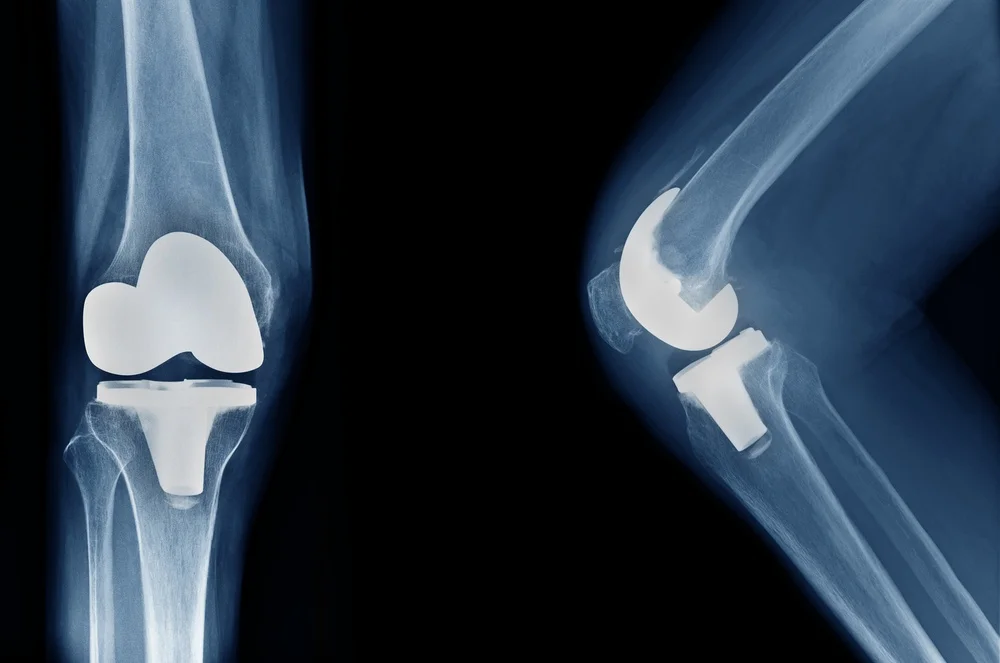

2. Total Knee Replacement (TKR): Restoring Full Mobility

Total knee replacement, or TKR, involves replacing the entire knee joint with an artificial implant. This procedure is ideal for individuals with severe joint degeneration or advanced arthritis, providing significant pain relief and improved joint functionality.

• Long-Lasting Results: Modern implants used in TKR are designed for durability, often lasting 15–20 years or more.